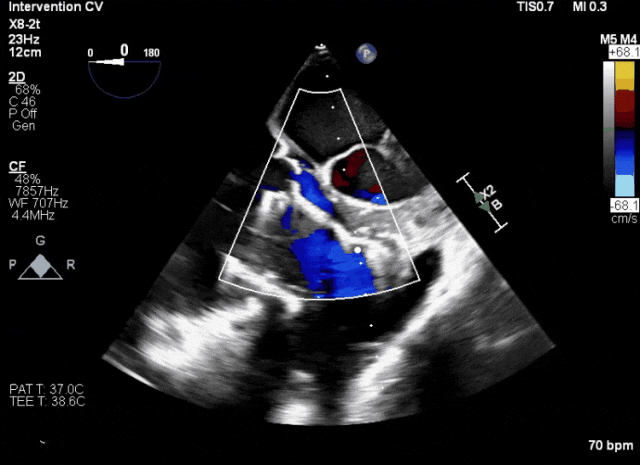

第二例患者手術(shù)難點(diǎn)

1、患者左心機(jī)械瓣術(shù)后,術(shù)中TEE成像有偽影干擾;2、三尖瓣重度反流,右心房、心室嚴(yán)重?cái)U(kuò)張致三尖瓣葉拴系,Gap:15.3mm,注意阻擋件抓取瓣葉操作。

術(shù)前超聲顯示三尖瓣重度反流合并拴系

術(shù)中TEE成像困難,偽影干擾